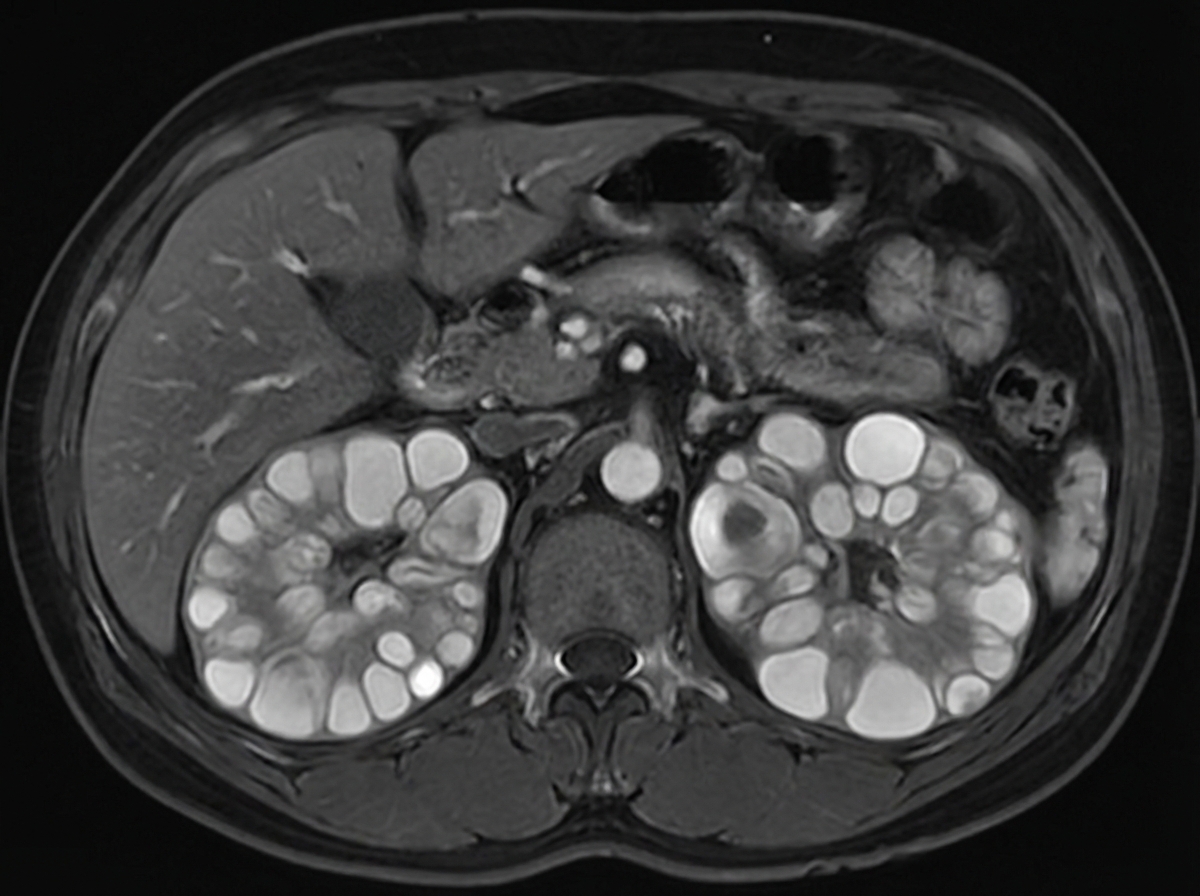

| Key Features | Massive bilateral cysts, enlarged kidneys, HTN, pain, hematuria, ESRD | Bilateral echogenic kidneys, small cysts (radial), oligohydramnios sequence (severe cases) |

ADPKD - The Dominant Disruptor

- Clinical Triad: Flank pain, hematuria, palpable kidneys. Hypertension common.

- Diagnosis (Ultrasound - Ravine modified for +ve family history):

- Age 15-39: ≥ 3 cysts (unilateral/bilateral).

- Age 40-59: ≥ 2 cysts in each kidney.

- Age ≥ 60: ≥ 4 cysts in each kidney.

- ADPKD: Most common inherited; PKD1 (chr 16) > PKD2; berry aneurysms, hepatic cysts.